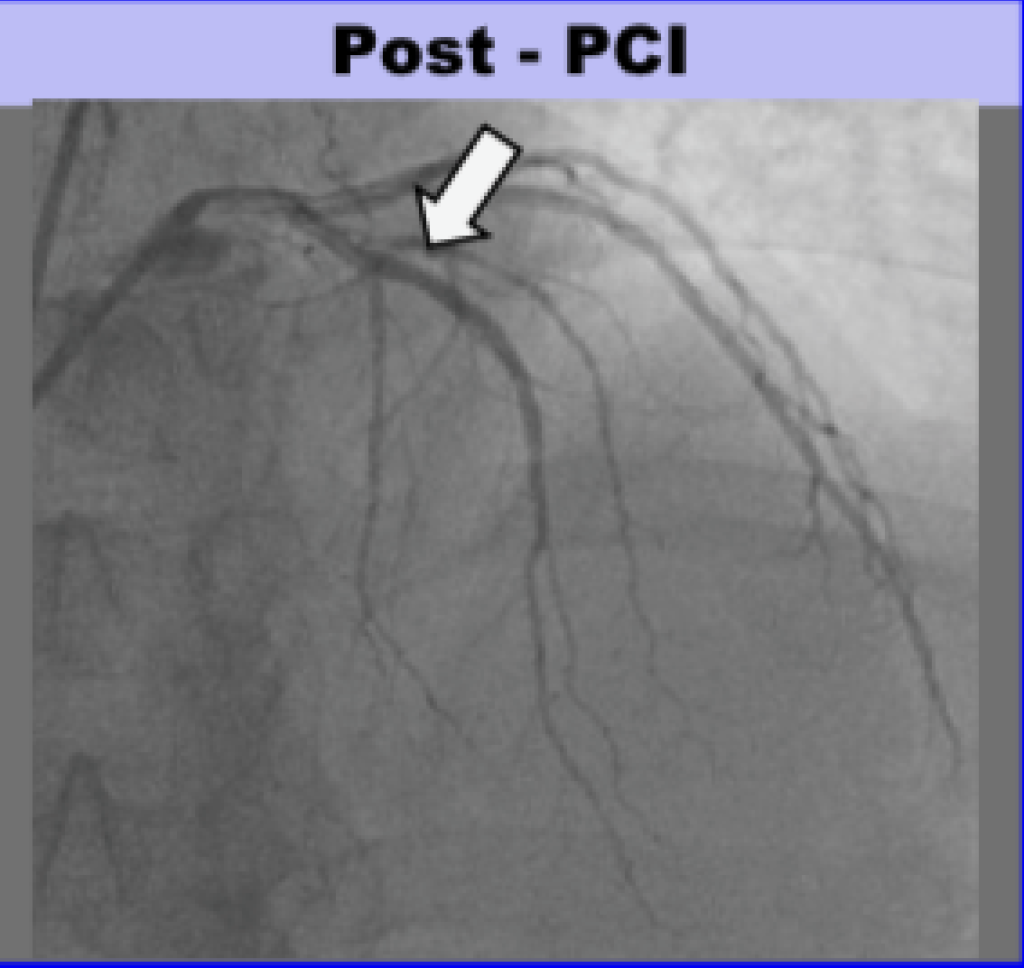

Angiogram

- There was a 100% ostial (very proximal) LAD occlusion. According to the schematic below, the occlusion was proximal to the septal perforator, with Septal OMI just as predicted. Frankly, it does not look like that to me but I am far from expert at angiograms.

Here is the angio before and after PCI, and a schematic:

Total time from door at outside hospital to balloon at PCI hospital was 88 minutes! (In transfer cases, guideline acceptable time is 120 minutes from first medical contact to balloon)